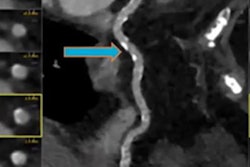

It's known that people with HIV are at increased risk of cardiovascular disease, but the prevalence and extent of coronary artery disease among HIV-positive people with low to moderate traditional cardiovascular disease risk has been unclear, the team wrote. Hoffmann's group used CCTA to investigate the specific factors associated with cardiovascular disease in people with HIV, and to assess levels of coronary artery disease.

The primary outcome of the study was prevalence and composition of coronary artery disease assessed by CCTA; exams were rated for the presence and composition of atherosclerotic plaque and the degree of stenosis. The team also explored whether there were any associations between coronary artery disease and typical risk factors and biomarkers in this population (such as insulin, interleukin 6, and C-reactive protein).